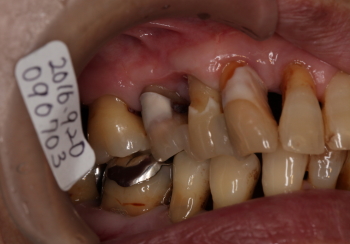

| 2016年09月20日 FOP(歯肉剥離掻爬術)の約2カ月後の状態。 同部を外科処置した翌日から痛みも、出血、排膿、腫脹、しみもなくなり予後良好。 ただし、歯間部分(14、15番間)の退縮が認められる。 |